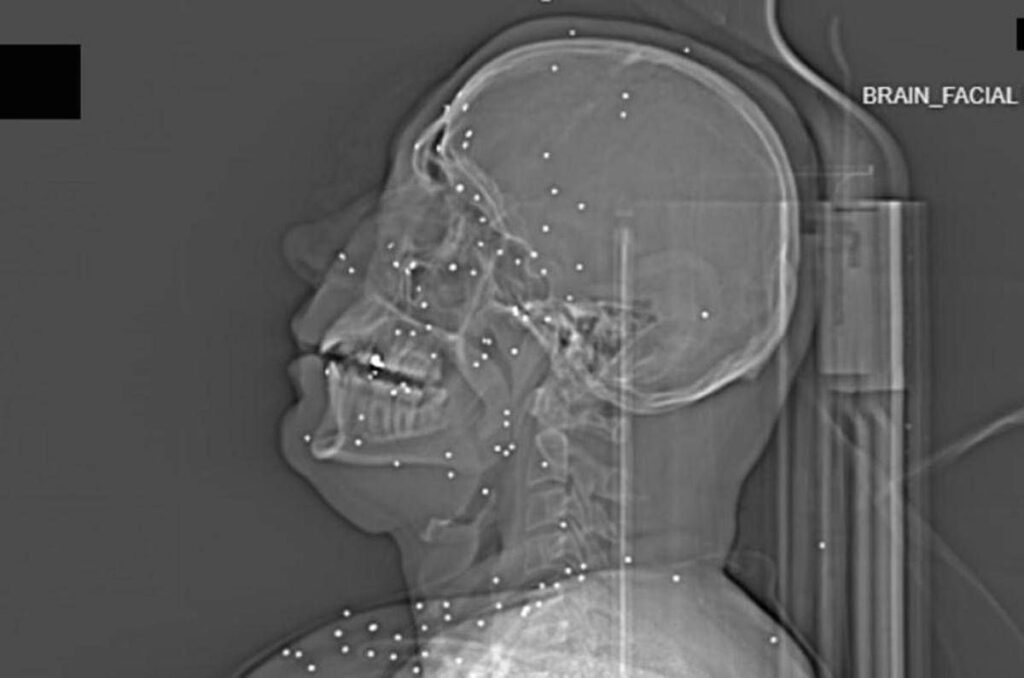

Il volto di Anahita – nome di fantasia, poco più che ventenne – appare come un cielo notturno attraversato da punti luminosi. Piccole sfere metalliche, da 2 a 5 millimetri, disseminate sul viso, nelle orbite oculari, persino nella massa scura del cervello. Sono proiettili “birdshot”, pallini da caccia sparati da un fucile a pompa. A distanza ravvicinata, spiegano gli esperti, non sono affatto “meno letali”: possono frantumare ossa, devastare tessuti molli, perforare facilmente un bulbo oculare. Anahita ha perso almeno un occhio, forse entrambi.

Quell’immagine non è un caso isolato. Fa parte di oltre 75 set di esami diagnostici provenienti da un singolo ospedale di una grande città iraniana, raccolti nel corso di una sola serata, durante la stretta repressiva di gennaio. Una concentrazione temporale che, già di per sé, racconta una dinamica da “mass casualty”, evento con numerose vittime simultanee, tipico degli scenari di guerra o dei grandi disastri.

Le valutazioni, condotte congiuntamente dal Guardian e dalla piattaforma di fact-checking Factnameh, sono state affidate a un panel indipendente di specialisti internazionali: medici d’urgenza, radiologi, esperti di trauma imaging e balistica. Un ex medico iraniano di pronto soccorso, anch’egli consultato, ha confermato la coerenza del software utilizzato per gli esami e l’assenza di segni di manomissione. Gli esperti precisano che, senza cartelle cliniche complete, non è possibile formulare diagnosi definitive sui singoli pazienti. Ma il quadro complessivo, spiegano, è inequivocabile.

Accanto ai colpi di grosso calibro, emerge con forza un altro elemento: l’uso sistematico dei pallini metallici. L’Iran è tra i pochi Paesi in cui le forze di sicurezza impiegano birdshot metallico. A lunga distanza, i pallini si disperdono e colpiscono indiscriminatamente. A distanza ravvicinata, diventano devastanti: decine, talvolta centinaia di micro-proiettili che penetrano simultaneamente nei tessuti.

Le radiografie raccontano questa brutalità in modo quasi didascalico. Il torace di Ali – anche qui, nome di fantasia – contiene oltre 174 pallini metallici concentrati nella cavità destra. Il polmone parzialmente collassato, circondato da sangue e gas. Secondo gli esperti consultati, anche con un intervento chirurgico immediato e massiccio, il rischio di morte rimane altissimo.

Ma non è solo la gravità delle ferite a colpire. Caso dopo caso, le immagini mostrano corpi colpiti al volto, al torace, ai genitali. Ventinove pazienti risultano feriti al viso da birdshot. Almeno nove presentano lesioni nell’area genitale o pelvica, provocate sia da pallini sia, in alcuni casi, da fucili ad alto calibro.